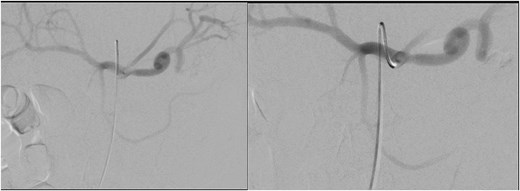

He was treated with tranexamic acid and blood transfusion due to bleeding as evident on computed tomography (CT) angiogram that was exacerbated in the setting of anticoagulation. He then underwent angioembolization with interventional radiology. The angiographic finding of a pseudoaneurysm arising from a pancreatic branch off the SMA was embolized (Fig. 9).

Angioembolization of pseudoaneurysm arising from pancreatic branch off SMA.